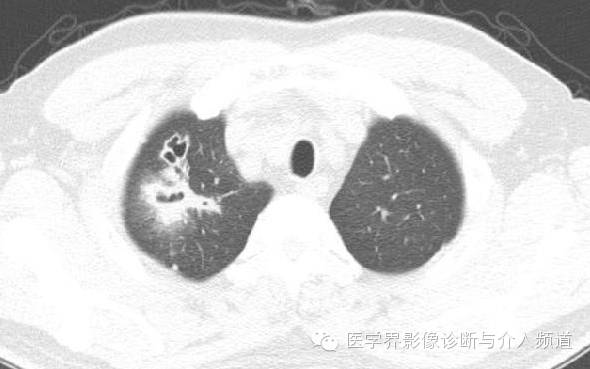

治疗前

CT显示右肺上叶实性团块病灶内不规则空洞形成,周围可见GGO,右侧胸腔少量积液。患者外周血嗜酸性粒细胞增多和Pw抗体阳性。治疗后X线平片显示右上肺结节影缩小。治疗前X线片显示病灶位于右肺上野,右侧肋膈角变钝。此外,X线平片示主支气管节段性偏心性狭窄,这是由于胸内甲状腺肿外在压迫所造成。